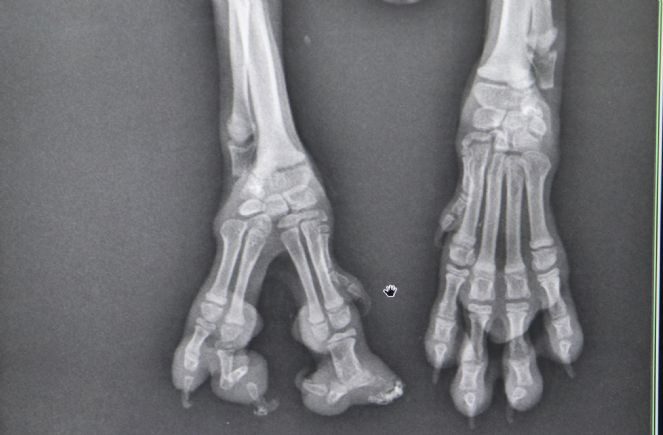

Kent merkezinde güzellik uzmanı olarak çalışan Fatoş Karaarslan, yaklaşık iki ay önce henüz 10 günlük ve sağ ön ayak parmakları doğuştan yapışık olan chihuahua cinsi bir köpek sahiplendi. ''Kahve'' ismini verdiği köpeğinin ayağındaki sağlık sorununu araştıran Karaarslan, bunun sindaktili (yapışık parmak) hastalığı olduğunu öğrendi. Veteriner kliniğine gigen Karaarslan, ameliyatla köpeğinin yapışık parmaklarının düzeltilebileceğini öğrendi ancak yaşı çok küçük olduğu için ameliyatı erteledi. Karaarslan, köpeği Kahve 2 aylık olduktan sonra tekrar Veteriner Hekim Mete Betin’in kliniğine geldi. Burada yapılan ameliyatla Kahve’nin sağ ayağındaki yapışık parmaklar birbirinden ayrıldı.

Ameliyatı yapan Veteriner Hekim Mete Betin, halk arasında yapışık parmak olarak bilinen sindaktili hastalığının genelde insanların ve hayvanların erkek cinsiyetinde görüldüğünü söyledi. Betin, “Çünkü Y kromozomundan gelen hatalı genetik aktarımı sonucu ortaya çıkıyor. Literatürde 2 binde 1 görülme olasılığına sahip bir hastalık olsa da Türkiye’de neredeyse milyonda bir oranda görülüyor. Ölümcül bir hastalık değil. Küçük bir estetik operasyonla can dostlarımız normal hayatına devam edebiliyor. Biz de ameliyatla Kahve’nin yapışık parmaklarını ayırıp sağlığına kavuşturduk. Eğer tedavi edilmezse hayvanlarda yürürken topallama, koşarken ağrı, sağlıklı olan ayaklara fazla yüklenme nedeniyle kas sisteminde zedelenme gibi yaşam kalitesini düşüren sorunlara neden olabiliyor” diye konuştu.